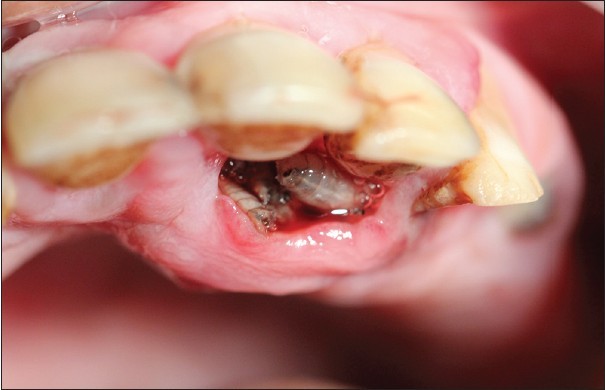

So, Oral Myiasis is a rare disease caused by the Larvae of dipterans. It is reported mostly in developing countries. Myiasis can occur in various parts of our body, not only in the oral region. It can be in the skin, nose, ear, eyes.

Those were some examples of genera. Mostly, it is Chrysomya bezziana (Old Screwworm or Screwworm). It is an obligate parasite; it needs some dead tissue for its species survival, propagation, and reproduction. Its female lays eggs in open wounds, ulcers, scratches, or mucous membranes.

Suppose any injury or cut occurs and remains in direct contact with the air and external environment or not banded properly in its treatment. In that case, it serves as an open wound. Ulcers happen when stomach acid damages the lining of the digestive tract. The mucous membrane is the skin and gingival of the mouth.

However, the treatment is the surgical removal of larvae. And the result of the activities of larvae is treated after its removal. Turpentine solution help in the extraction of maggots.